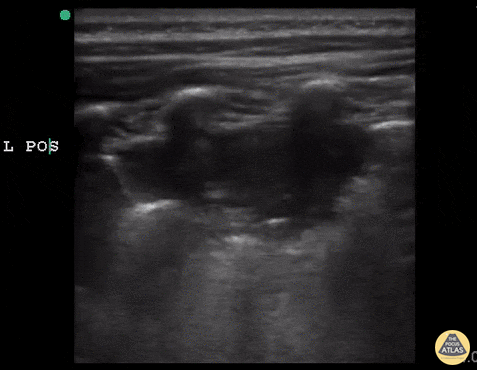

6 y/o sickle cell (HbSS) coughing with left-sided chest pain and 1 day of fever. Lungs without crackles, good air entry bilaterally. A consolidative process is seen with a hypoechoic region with posterior enhancement greater than 1cm in an area where normal A lines should be present. This is highly suggestive of acute chest syndrome given clinical features. Dr. Sathya Subramaniam, Pediatric EM Fellow - Kings County/SUNY Downstate